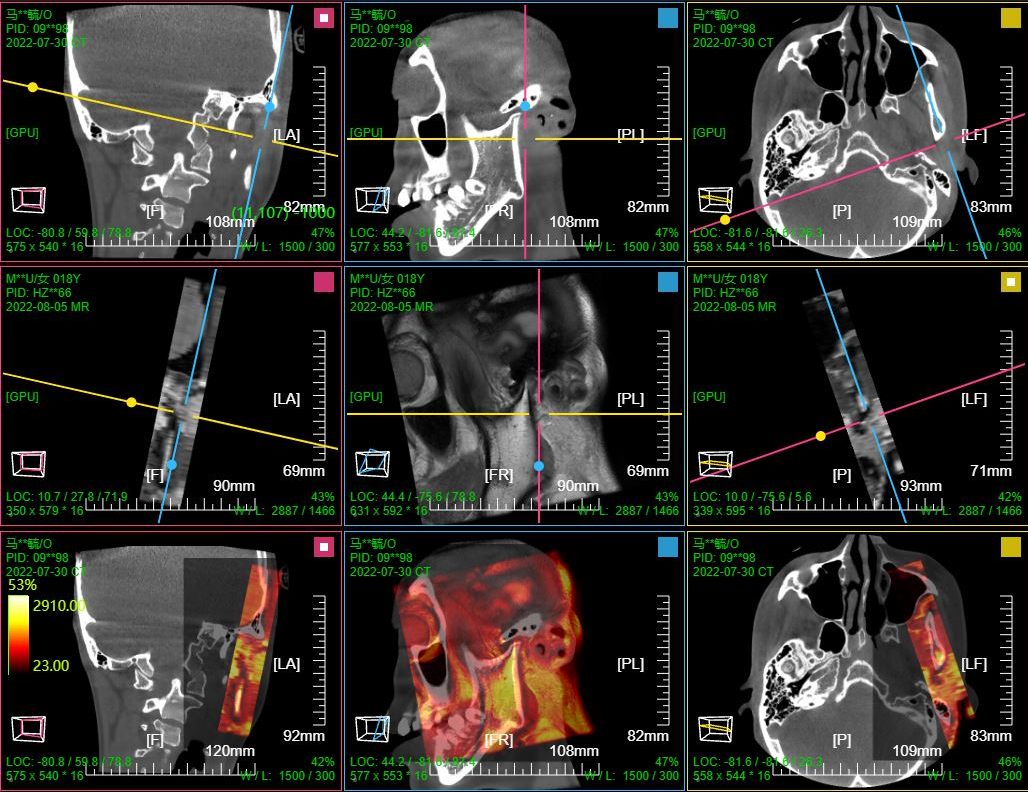

- 支持PEPTCT融合,三维MPR/MIP融合; XA数字减影;影像增强;

七、PET CT / MR融合功能操作和截图

二维融合,三视图显示;滚动滚轮三个序列窗口联动;

三维融合; 支持 MPR 9窗口视图;MPR+MIP 12窗口视图; (AXIS或CORO或SAGI)切片+MIP 6窗口视图

PT序列MIP窗口滚轮默认水平旋转; 其它序列MIP窗口滚轮默认缩放

PT序列MIP窗口左键默认缩放; 融合序列MIP窗口左键默认移动; CT序列MIP窗口左键默认旋转

点击MPR窗口右上角颜色块可AXIS轴位、CORO冠位、SAGI矢位切片切换

鼠标右键点击MPR窗口左下 切片位置指示器 可显隐十字交叉线; 左键点击MPR复位

鼠标左键点击MIP窗口左下 三维旋转状态指示器 可快速旋转到指定面; 右键点击三维旋转复位

PT序列MIP窗口拖动 "绿色X" 自动计算并定位最大SUV点位置并定位十字交叉线刷新显示MPR

CTMR配准融合